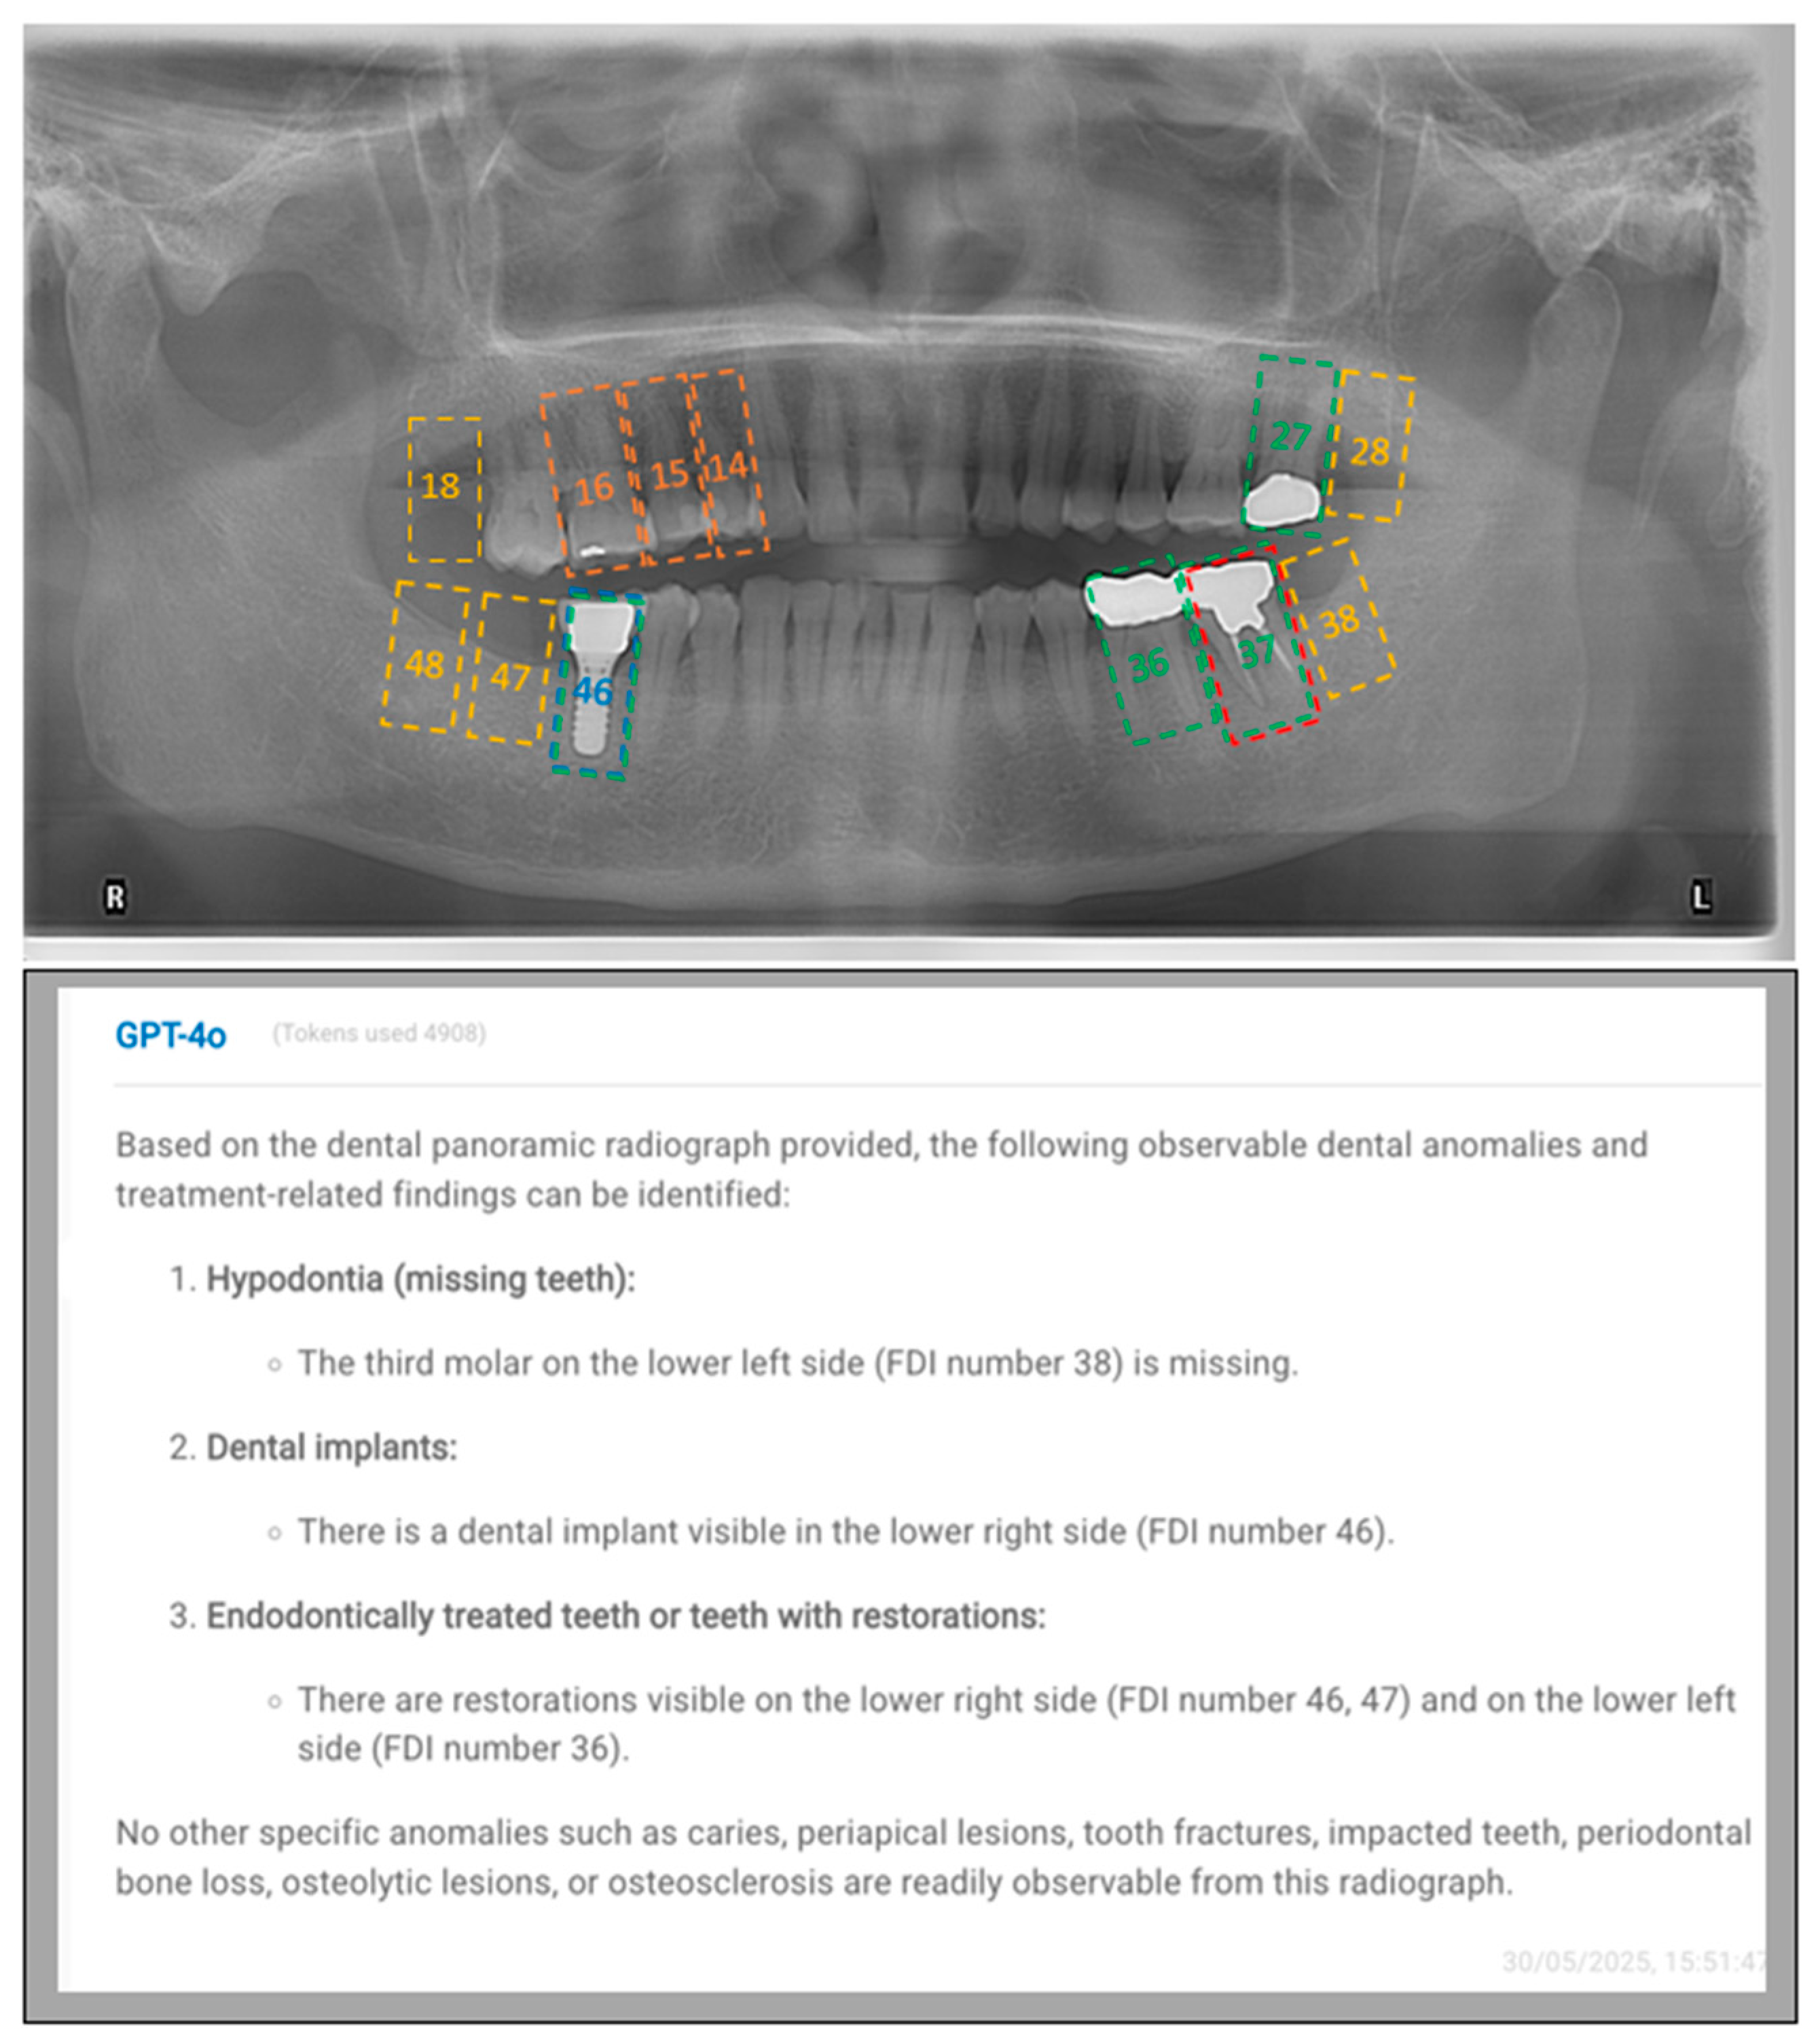

- “This is an anonymized dental panoramic radiograph from a research study. You are assisting in identifying observable dental anomalies as listed below, and specify the FDI tooth number of identified items. Focus only on visual patterns, not diagnoses.

- Developmental anomalies:

- Hypodontia (missing teeth) or anodontia.

- Dental anomalies:

- Caries (radiolucent lesions in enamel/dentin).

- Periapical lesions (e.g., radiolucency at root apex indicating infection or granuloma).

- Tooth fractures, cracks, or retained roots.

- Impacted teeth (e.g., third molars, canines).

- Bony anomalies:

- Periodontal bone loss (horizontal/vertical reduction in alveolar bone height).

- Osteolytic lesions (e.g., cysts, tumors like ameloblastoma or odontogenic keratocyst).

- Osteosclerosis (abnormal bone density, e.g., condensing osteitis).

- Iatrogenic/treatment-related findings:

- Endodontically treated teeth or teeth with restorations (Fillings, Crowns or bridges).

- Dental implants (screw-shaped radiopaque structures).”